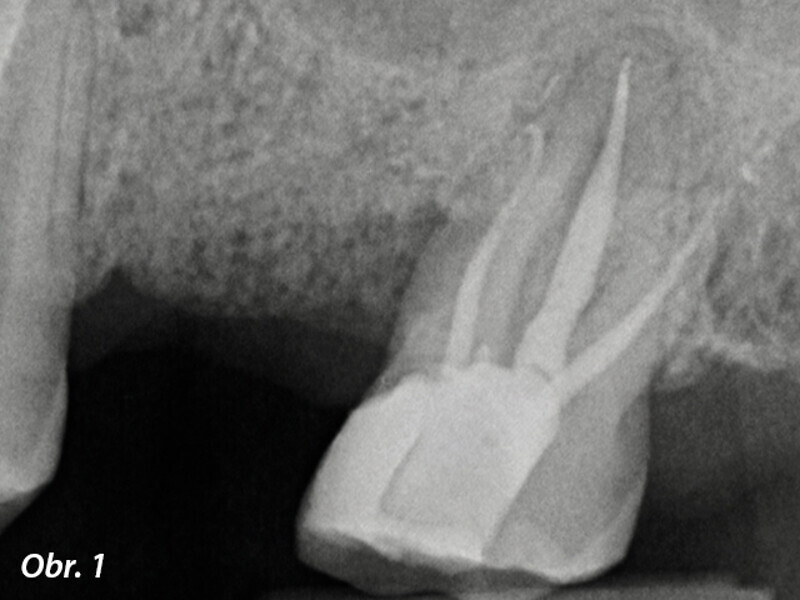

3D technologie v diagnostice a léčbě endodontických onemocnění